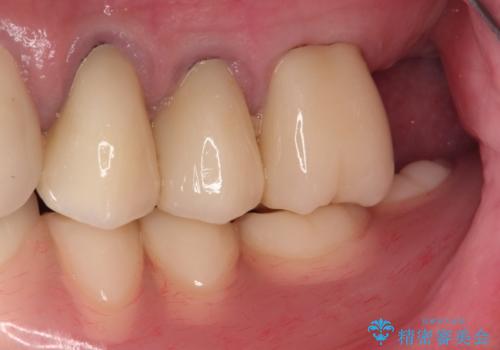

奥歯が欠損しており、上下の前歯が強く咬合する可能性があったので、上顎前歯の裏側は金属のものにしました。

お忙しい方でしたので、治療が終了するまでにじかんがかかってしまいましたが、奥歯でもしっかり咬めるようになったと喜んでいただけました。